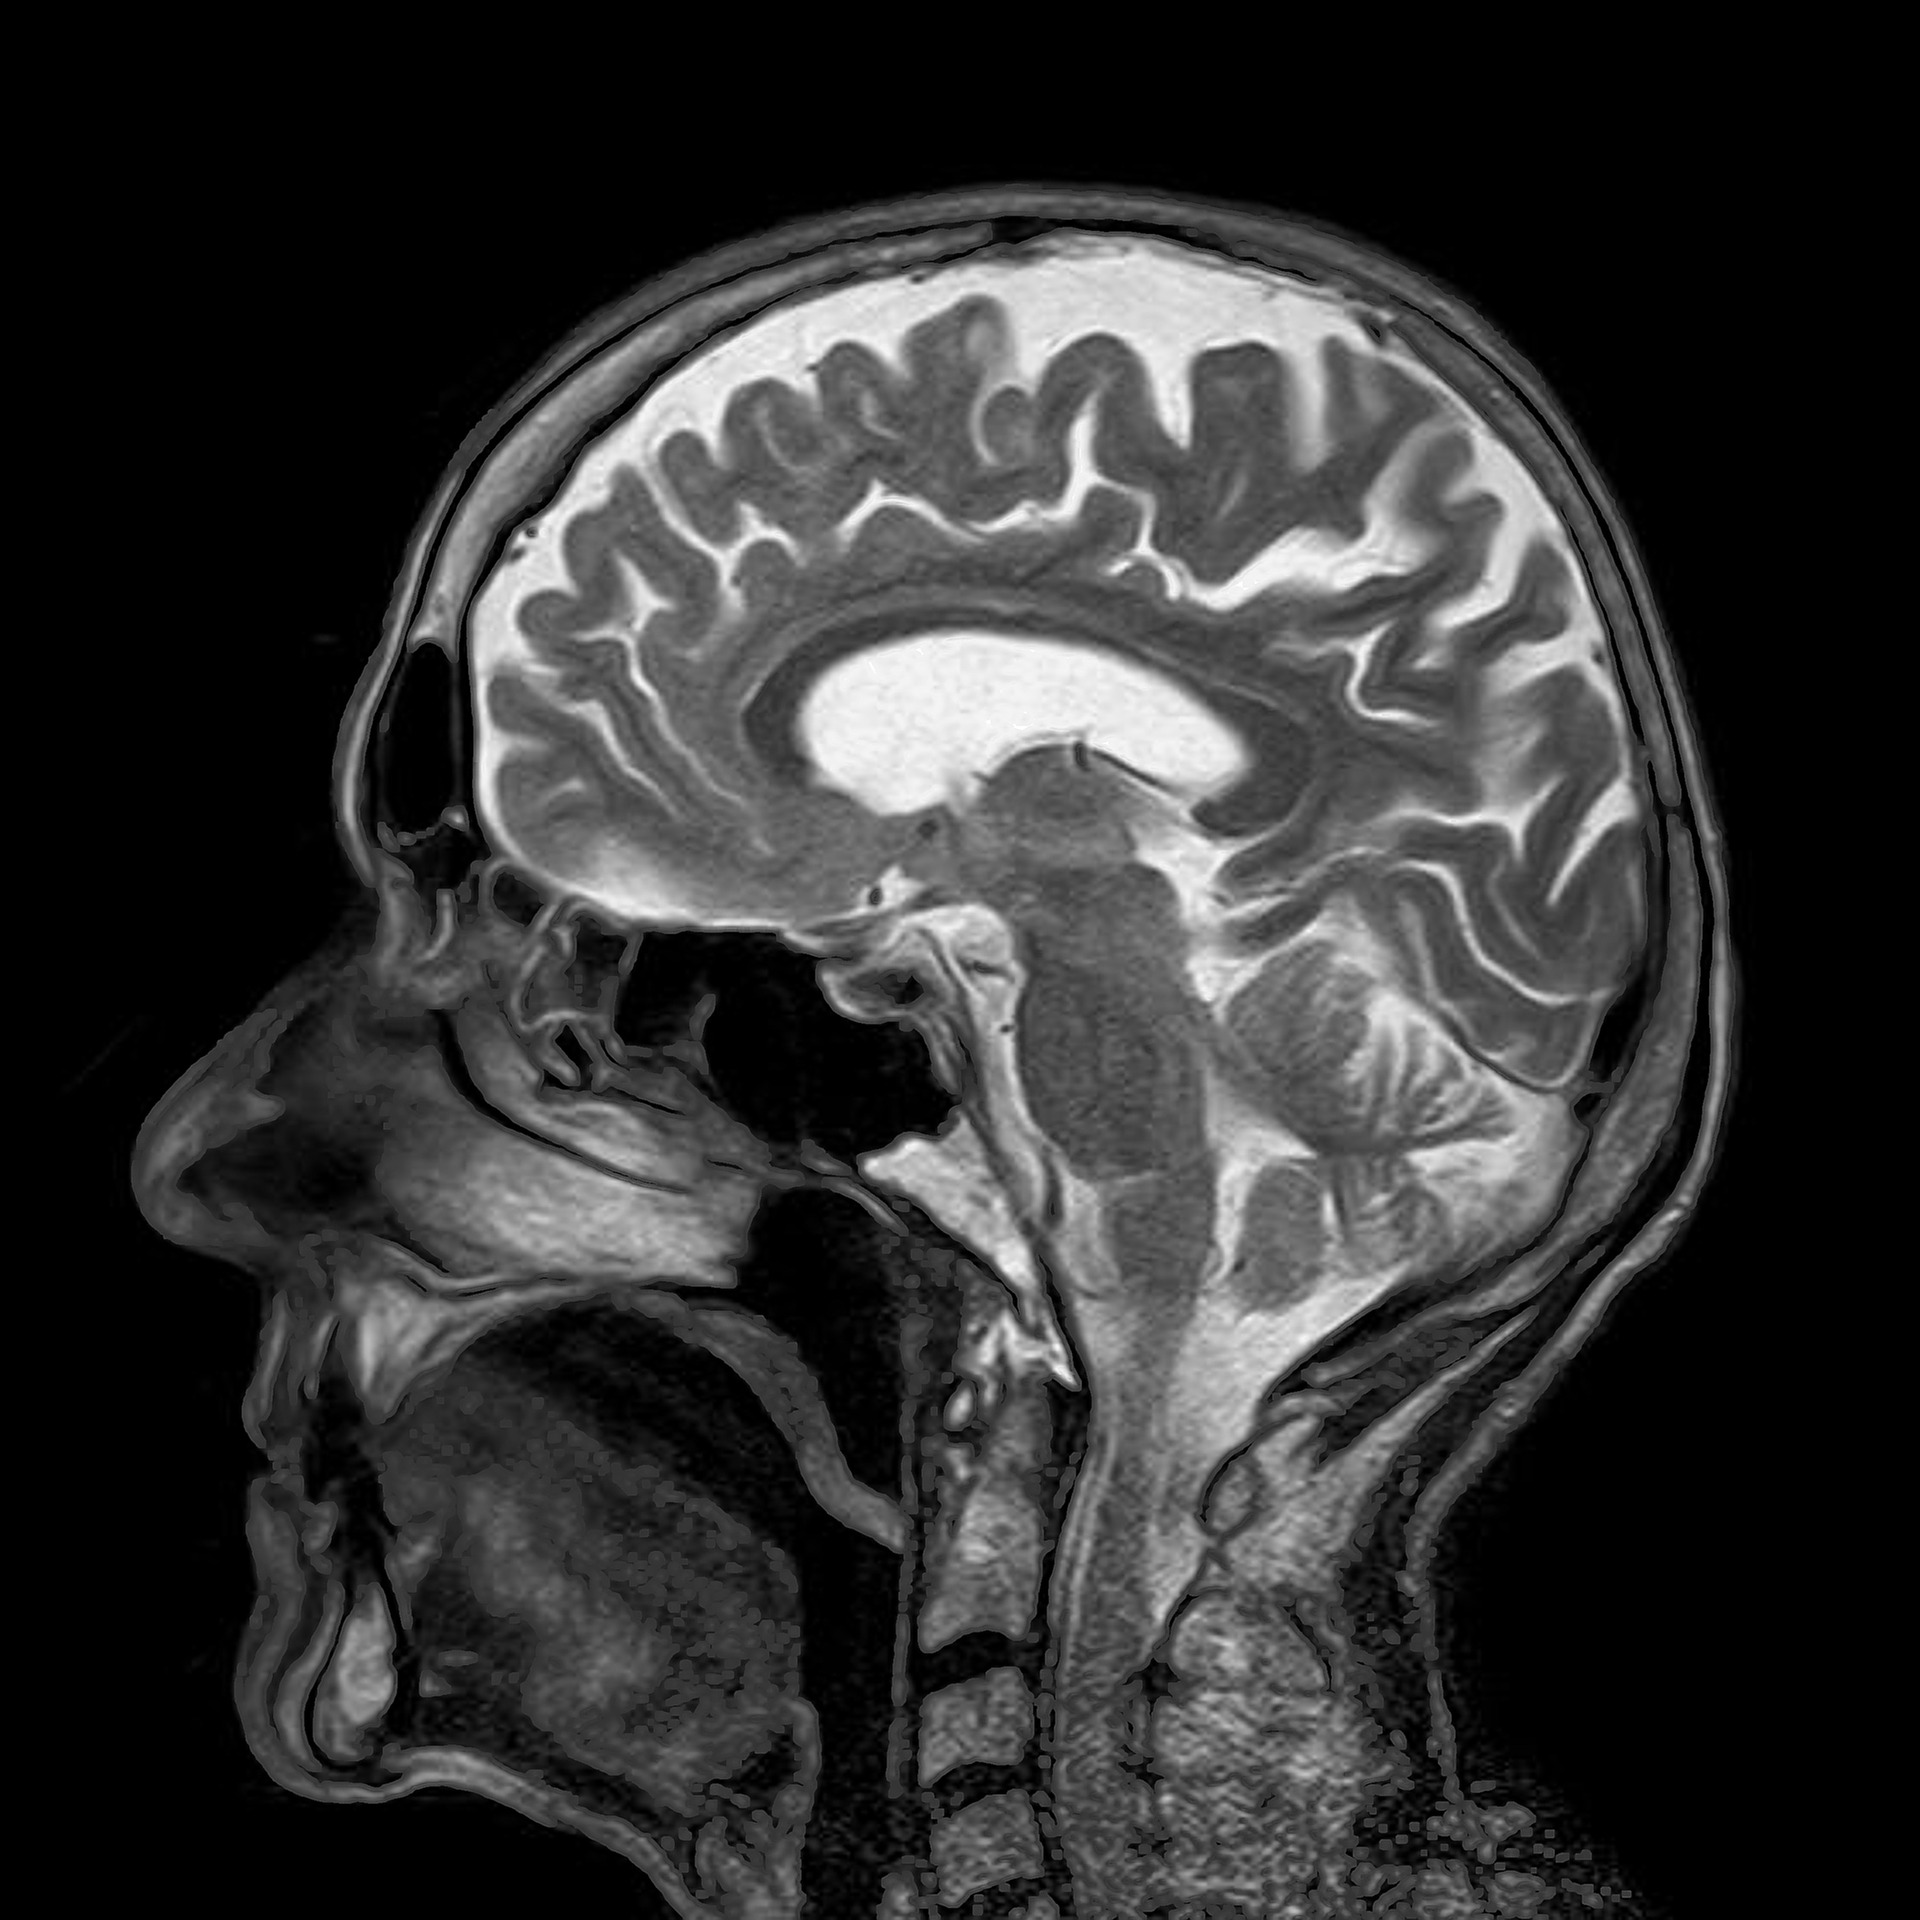

뇌 과학 분야에서는 뇌파 측정 및 MRI 등으로 명상이 뇌에 미치는 효과를 과학적으로 분석할 수 있게됐다. 미지의 추상적이고 정적인 분야에서 과학적으로 측정하거나 분석이 가능해진 분야로 변화되었으며 이를 이용한 다양한 연구가 활발하게 진행 중이다.

명상에 관해서 밝혀진 과학적인 연구결과는 대표적으로 티베트 수행자의 뇌 활동 분석이 있다. 불교 수행자의 뇌파를 분석 한 결과, 인식 활동과 관련된 감마파 뇌파의 활동량이 명상 수행에 소요된 시간의 길이에 비례하면서 증가하고 있는 것으로 나타났다. 이것은 집중력의 증가와 관련이 있다고 알려져 있다. 즉 명상을 지속하면서 집중력이 증가 한것이다.후속 연구에서는 명상하는 이 티베트 수행자의 뇌의 형태에서도 변화가 일어났던 것으로 밝혀졌다. 생각과 창의력을 담당하는 전두염 피질이 두꺼워지는 구조 변화를 볼 수 있었고, 공포와 불안, 기쁨, 슬픔 등의 감정에 작용하는 편도체와 전두엽 피질의 결합이 더 강력하게 결합하는 것도 밝혀졌다. 이 결과에서 유추할 수 있는 것은 감정을 제어하는 능력이 높아질 수 있는 가능성이 있다는 것이다. 연구 대상이 된 티베트 불교의 수행자는 하루에 약 9~10시간씩 3년간에 걸쳐 명상을 하고 있었는데 명상을 통해 자신의 뇌의 활동 방식을 스스로가 변화시키고 있었던 것이다. 명상을 통해 뇌의 구조를 바꾸고 집중력을 증가시키며, 감정을 컨트롤할 수 있게 된 것이다.